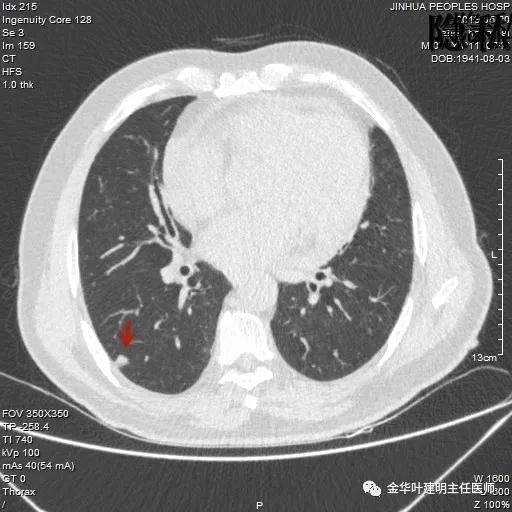

如果我们把各个时候的片子放在一起对比,就会发现右下叶背段的空腔性病灶是从无到有,并逐渐进展的:

逐渐进展的空腔性病灶,特别边缘还是磨玻璃样的,需要特别当心,虽然有的层面看上去似肺大泡,但仍需我们提高警惕,注意必要的随访复查。

考虑恶性,那么就得考虑住院并行手术治疗,入院后再进一步查靶扫描,结果如下:

是不是囊腔型腺癌?周围病灶,有空腔,有磨玻璃成份,当然要考虑,但我觉得因为似乎是以往是空腔性病变,今年其内部分填充了实性成分,要考虑粘液腺癌可能为大。当然反正都得手术切除治疗。